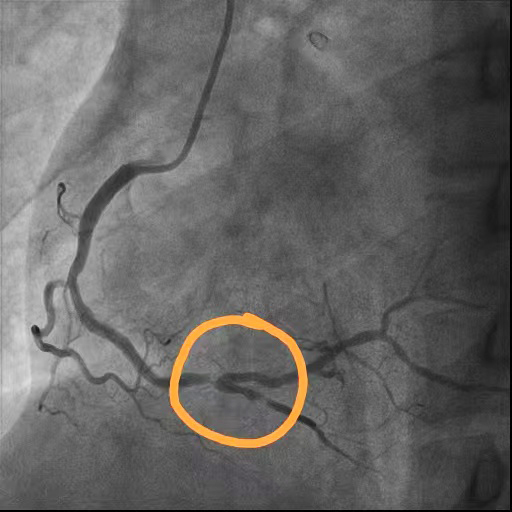

右冠脉狭窄

术后

右冠脉狭窄解除